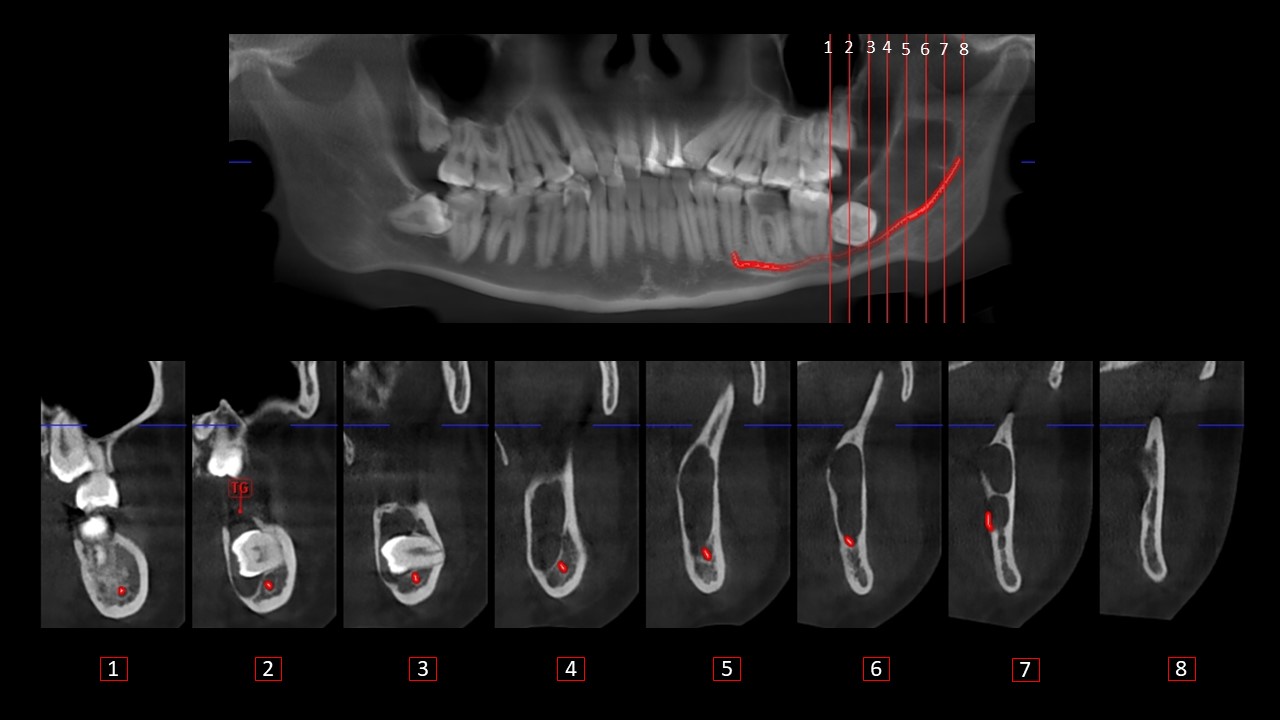

Figura 5

En los cortes transaxiales(Figura 5), se observa el aumento de la densidad ósea a nivel apical de pieza 37 (corte 1), la presencia del tracto gubernacular de la pieza 38 que comunica la lesión con la cima del reborde alveolar (corte 2) y la trayectoria del CDI (cortes del 1 al 8).